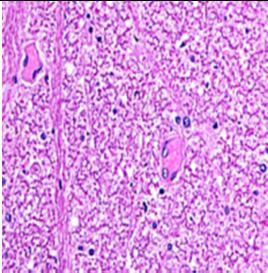

Fig. 10: Images of Spinal Cord after histopathology of group 1 to group 3.

Group 1: Inflammation, Severe nuclear and neuronal cell loss was observed.

Group 2: Mild nuclear and neuronal cell loss was observed.

Group 3: Mild nuclear and neuronal cell loss was observed.

In present study “Efficacy of Jambu (Seed) as an Antidote in Kuchala Poisoning an Experimental Study” histopathological report of brain showed mild rejuvenate of degenerate neurons, hippocampal oedema was observed and histopathological report of Spinal cord showed mild nuclear and neuronal cell loss was observed.